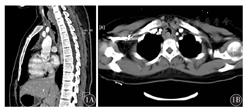

以2009年4月至2014年2月本院诊断的4例气管、支气管ACC患者为研究对象。其中男性2例,女性2例;年龄23~65岁,平均年龄43.8岁。主诉症状均有反复刺激性咳嗽,从出现症状到确诊时间为2~72个月,平均23.5个月。4例胸部CT示气管或支气管管壁不均匀增厚或不规则软组织密度影,边界不清(图1)。4例患者中1例行气管切开肿瘤切除术,1例行肿瘤处气管节段切除术;其余2例患者仅作纤维支气管镜活组织检查,2例行纤维支气管镜检查示气管或支气管腔内呈菜花状或结节状新生物,表面粗糙、质硬,而未接受手术治疗。手术切除及活组织病理检查诊断均为ACC。

ACC又称"圆柱瘤",主要发生于涎腺组织,乳腺[4]、前列腺[5]。气管、支气管腺样囊性癌罕见,其发病率仅占原发性肺肿瘤的0.1%~0.5%,男女发生比率相当,发病高峰年龄为40~50岁[6]。本组患者男女比例1∶1,发病年龄23~65岁,平均年龄43.8岁,与上述报道文献基本一致。ACC 90%以上起源于气管、主支气管黏膜下腺体,多位于大气道且生长缓慢,病史较长,早期症状不典型,主要表现为中央气道阻塞症状,如呼吸困难、喘鸣等,临床易误诊为支气管哮喘或慢性支气管炎而延误治疗[2,3]。本组患者从出现症状至病理确诊时间为2个月至6年,患者主要表现为刺激性咳嗽、咳痰、痰中带血等。1例临床误诊为支气管扩张症并治疗长达6年,其余3例按支气管炎抗感染治疗2~12个月。本组4例患者影像学表现为气管、支气管管壁不均匀增厚或不规则软组织密度影,2例纤维支气管镜检查示气管或支气管腔内新生物,表明对于长期出现刺激性咳嗽、痰血及呼吸困难的患者需要提高警惕,及时的影像学及纤维支气管镜检查有助于早期诊断。